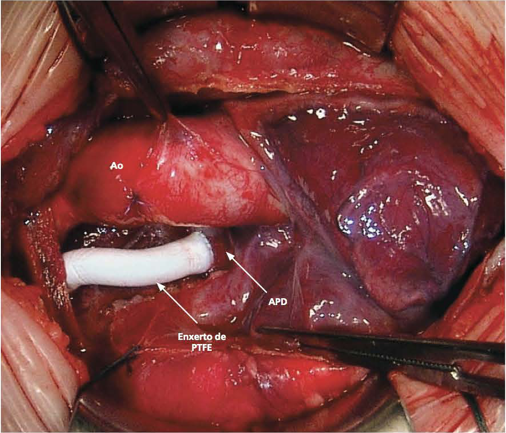

A transposição das grandes artérias (TGA) associada a outras anormalidades cardíacas apresenta grandes desafios. Cerca de 30% de todos os…

Figura 1. Desenho anatômico do canal arterial. Fonte: cortesia do Dr. Mansuor Chaer Alameddin para esta publicação. O canal arterial…